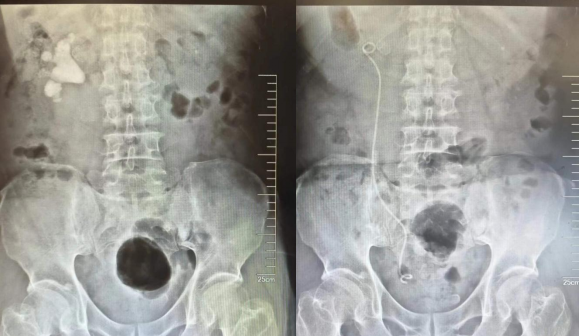

家住园区的徐大爷最近上厕所时发现小便颜色有点红,但没有其他任何不适感,起先没当回事,但接下来的一周该情况一直持续,徐大爷担心,便来到了独墅湖医院泌尿外科门诊。接诊医生听了徐大爷的讲述,为徐大爷做了泌尿系彩超和尿常规检查,彩超结果着实让人吃了一惊:徐大爷的肾脏里竟长满了结石。进一步了解病史得知,徐大爷很多年前就做过肾结石和肾囊肿的手术,但术后一直没有腰酸腰痛等不适症状,也就没有再进行复查。接诊医生当即建议徐大爷住院做进一步的检查治疗。

入院后的CT检查提示徐大爷肾脏内充满结石,属于泌尿系结石中治疗难度最大的“完全无积水鹿角型结石”。更为棘手的是,术前检查还发现,徐大爷的心脏有明显增大,主动脉瓣重度反流,心功能较差。面对这样一例复杂的肾结石病患,泌尿外科浦金贤主任组织多次病例讨论,分析病情,研究最佳手术方案。

最终,在浦金贤主任指导下,周守军主任团队采用分期手术方式,一期行微创经皮肾镜,超声引导下穿刺肾脏后组下盏,顺利清除肾脏下盏、肾盂及上盏结石。二期行输尿管软镜手术,配合体外碎石,顺利清除残余结石。